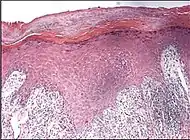

| Lichen sclerosus | Hyperkeratosis, atrophic epidermis, sclerosis of dermis and dermal lymphocytes.[7] | ![]() | ||